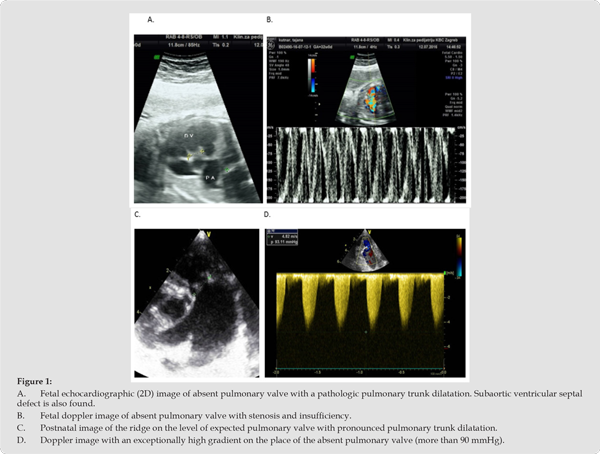

Consequently, they had RVH with suspicion of non-compaction right ventricular cardiomyopathy, more so in patient 4 than in patient 2 (Figure 1A-1D. – patient 2 and Figure 2A-2D-patient 4). Anomaly of ductus arteriosus is suspected in both of patients; in patient 2, a small, restrictive anomalous duct, through which only LPA is supplied, and which is separated from TPA (Figure 3A-3D - patient 2), in patient 4 there is an atypical, wide, tortuous arterial duct through which it enters the TPA, and then through the deficient PV into the RV. Massive insufficiency behind the trunk of the pulmonary artery towards the right ventricle is shown, and then the right ventricle with severe non-compaction cardiomyopathy (Figure 4A-4D - patient 4). In the other two patients, the ductus was not noted in the foetal cardiological examination. Interestingly, all pregnant women had problems during pregnancy; two had gestational diabetes mellitus and arterial hypertension, one had foetal hydrops and cystic hygroma (termination of previous pregnancy at 14 weeks), and one had a previous spontaneous abortion of unexplained aetiology. There is no information on any drug therapy during pregnancy.

In the postnatal diagnosis, all patients had dilatation of the right atrium, insufficiency of the tricuspid valve of varying degrees, dilatation and hypertrophy of the right ventricle, and clear changes in the defective pulmonary valve, which was the cause of severe stenosis in three patients (1,2,3), with a gradient of 60-90 mmHg (Figure 1D, patient 1), and all of them simultaneously had severe insufficiency in the same level of degree II-III, and in patient 4 only severe insufficiency dominates without registered stenosis (Figure 2C, pat. 4)). We reliably found pathological DB in three patients (2,3,4), with the fact that one duct was constricted and directed into the hypoplastic left PA that was separated from the right (Pat. 2) (Figure 3B,C & D, Pat. 2) in the frame of the TF type.

One DA was aneurismatic dilated (Pat. 3), and one was atypically tortuous and wide (Figure 4, Pat. 4)). A ductal anomaly should also be suspected in the first patient (Pat. 1) who was born as a premature child, but it was not diagnostically verified in the period until it theoretically could have closed delayed (3 months after delivery), but a complete absence of the ductus is also possible because it is the socalled TF type of APVS. In addition to the aneurysmal expansion of the TPA, all patients also had marked dilatation of the RPA, and only one had extremely wide both branches of the pulmonary artery (patient 3). We note that as many as three patients had hypoplasia of the left branch of the pulmonary artery (patients 1, 2, 4) (Figures 3 & 4), and patient 2 had extreme hypoplasia of the LPA, which filled through the restrictive DB, and was initially completely separated from the RPA. In patient 3, in whom VSD was mentioned prenatally, we did not find it postnatally, and two patients (pat. 1,2) had right-sided anomalies with subaortic VSD. We did not use the term TF anywhere with certainty because we believe that the basic characteristic of TF is a significantly smaller pulmonary artery than the aorta, while our patients with VSD (pat. 1 and 2) had a significantly wider PA than the aorta. The mean pulmonary artery pressure (mPA) in one patient (pat. 1) was 31 mmHg (measured at the age of 11 months), and the other patients had mPA below 25 mmHg. (pat. 2,3,4).

The patient received an early Contegra conduit, the VSD was closed, the LPA was connected to the TPA, and a stent was implanted in the LPA with ligation of the atypical, stenotic duct through which the LPA was supplied. In addition to this description, we find other similar descriptions [9,24]. The most recent report on the importance of the pathological form of the Botallo’s duct for the development of right-sided lesions described within the concept of APVS was given by Gewillig in 2017 on the example of 27 fetuses diagnosed with a dysfunctional Botallo’s duct [8]. He believes that various anomalies of the duct may be the reason for changes in the right heart, primarily in the pulmonary valve, and then in the pulmonary blood vessels. He mentions ductus obstruction, transient constriction, kinking (kneelike fold) and aneurysm, i.e. tortuous and wide ductus of Botallo [25]. He also mentions the right ventricle as a potential site of suffering, including the development of non-compaction cardiomyopathy. Our paper describes in detail an isolated form of APVS (patient 4) who had a wide, tortuous (siphonic) ductus (early ligation), and in addition to other described anomalies, had severe non-compact cardiomyopathy of the right ventricle (see Figures 2 & 4).